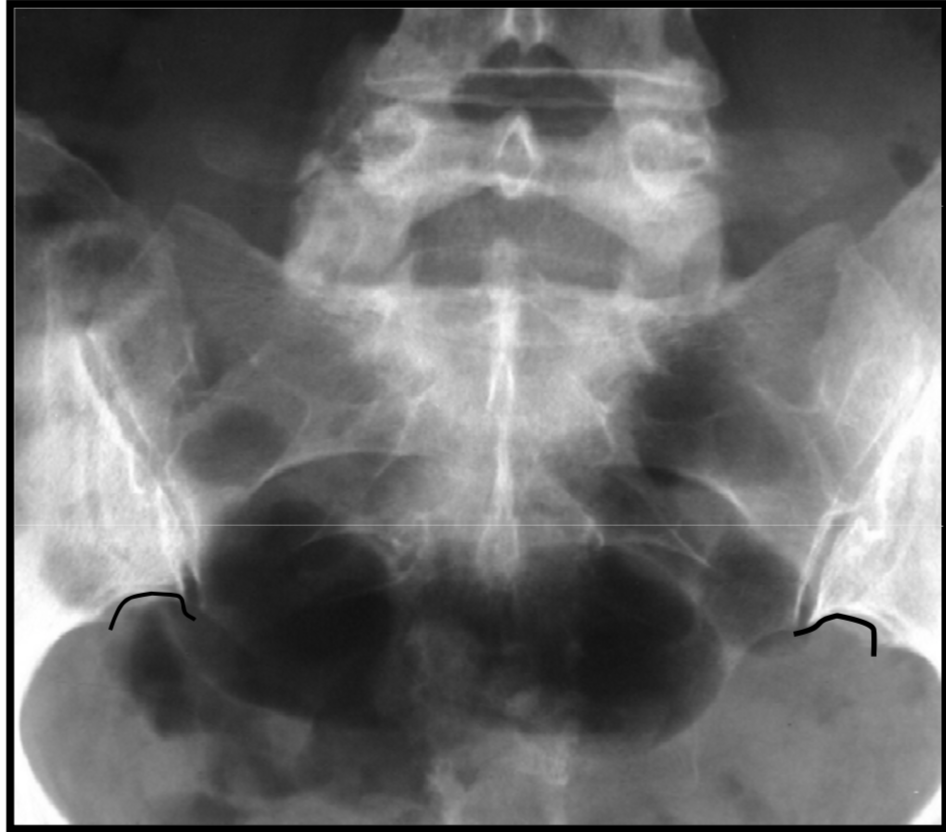

Pubic ears – another degenerative enthesopathy

anat variation

Phlebolith’s (calcified venous thrombi)